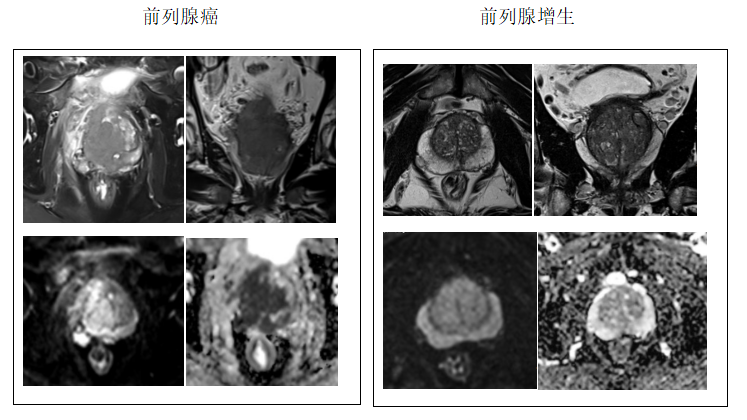

前列腺癌

更是悄悄成为了威胁中老年男性健康的 “沉默杀手”

它早期特别会 “装”

症状跟咱们常说的前列腺增生差不多

都是尿频、尿急、尿不尽

让人傻傻分不清

医生常会安排做个前列腺磁共振来 “火眼金睛”